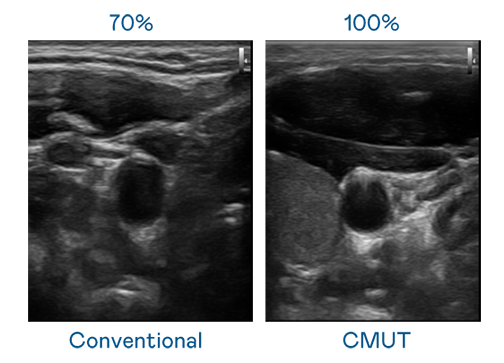

CMUT 技术是一种用电容式微机电元件来产生超音波讯号的技术。与传统 PZT 压电式技术相比,CMUT 频宽增加 30%,更宽频的超音波讯号让影像解析度大幅提升,是实现高影像品质医疗超音波扫描、促进精准医疗发展的关键技术。

大频宽带来超清晰影像

超音波影像的解析度高低,首先取决于探头能发出的讯号频宽。MG不朽情缘 CMUT 可提供高清晰的超音波讯号,提供高频宽、高灵敏度、影像纹理细节更高的超音波影像,协助医护人员缩短影像判读时间及利用精准的医疗影像进行诊断。